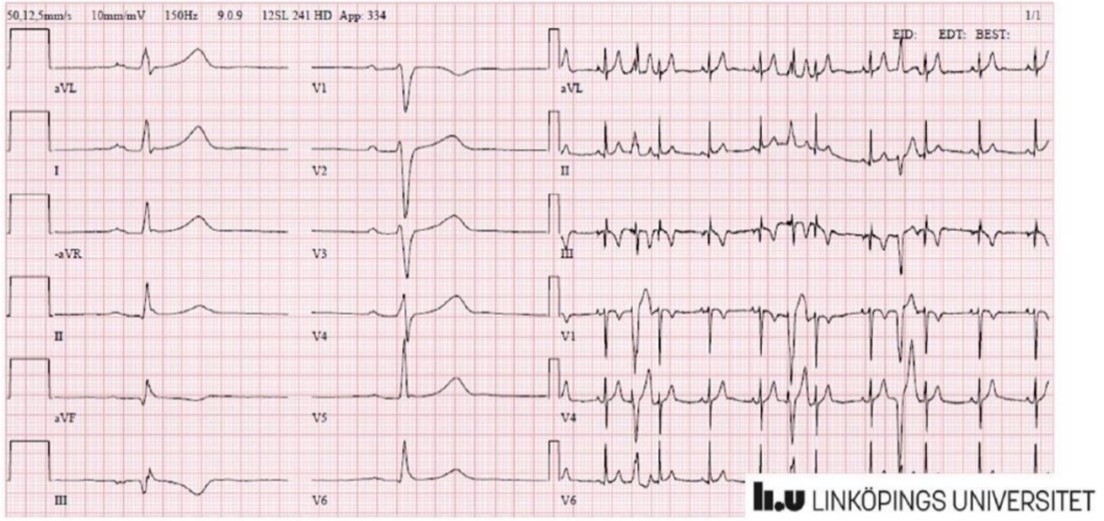

Tolka bilden

ICD (över vänster lungfält) (intern defibrillator)

- Spridda smånodulära förändringar bägge lungor

- För mkt små spridda förändringar höger (framför allt) även vänster

Lungröntgen visar

- I bägge lungor smånodulära förändringar